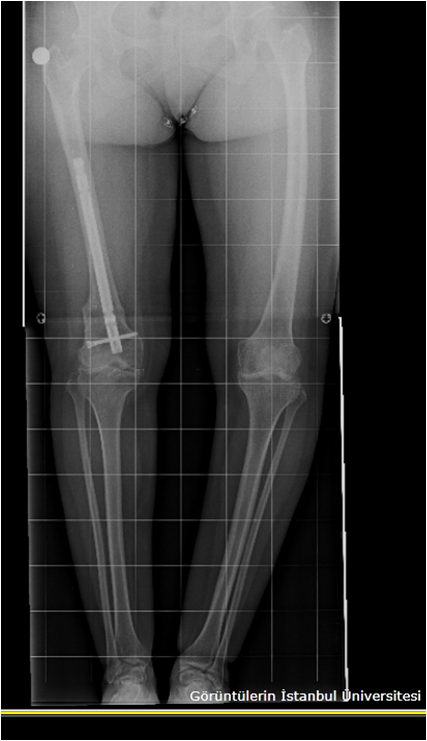

arthritis deformity surgery endoprosthesis hip prosthesis ilizarov ilizarov surgery infected nonunion knee prosthesis lengthening surgery limb lengthening surgery nonunion periprosthetic infection psodoartroz revision surgery total hip prosthesis total knee prosthesis